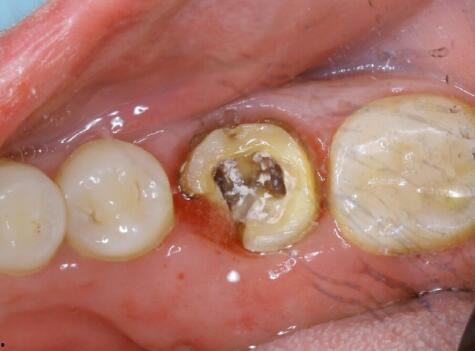

这张图片展示了一颗严重蛀牙的大牙,可以看到牙洞深不见底,仿佛一个黑洞,让人不禁为牙齿的主人捏一把汗。

这张图片中,我们可以看到一颗蛀牙旁边的好牙,两者形成了鲜明的对比。蛀牙黑洞般的牙洞,让人对牙齿健康产生了深深的担忧。